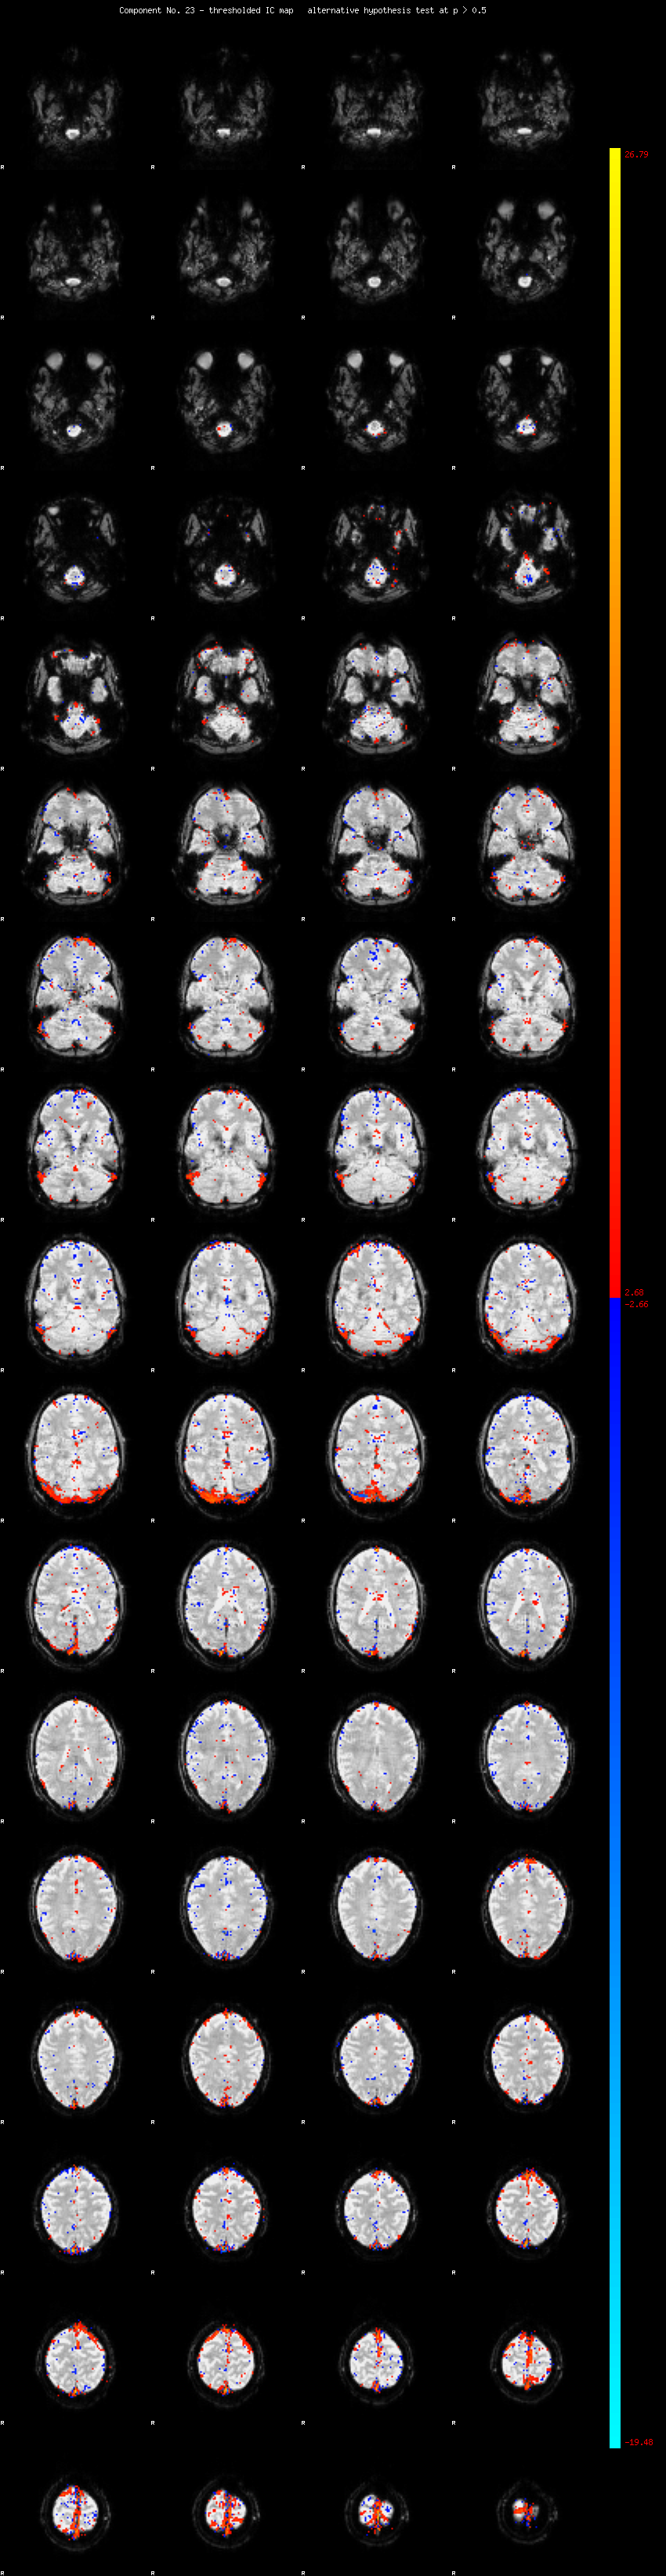

MELODIC Component 23

1.28 % of explained variance;     0.85 % of total variance